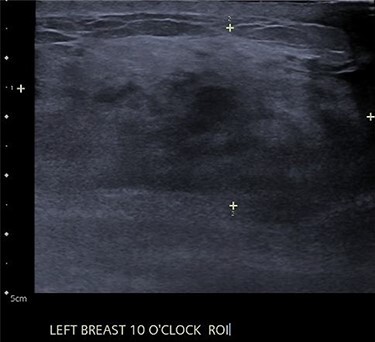

An ultrasound of the left breast demonstrated a 60-mm irregularity with no underlying collection at the 10 O’clock position, 2 cm from the nipple (Fig. 1). AB was treated with 5 days of oral flucloxacillin for presumed mastitis, and underwent a bilateral mammogram and ultrasound due to the suspicious irregularity of the left breast lesion. This showed an area of asymmetric density in the medial left breast with hyperemia (Fig. 2). The right breast showed two clusters of pleomorphic microcalcifications in the upper outer quadrant, further characterized as irregular lesions measuring 16 × 11 × 11 mm and 9 × 10 × 7 mm (Fig. 3).

Figure 1 .

Left breast ultrasound of granulomatous mastitis.